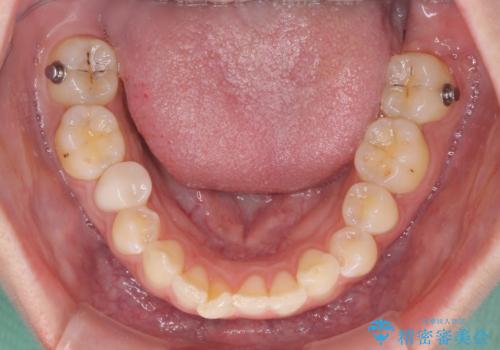

- 前歯の歯列不正を気にして来院された患者様です。

インビザラインでの矯正治療を希望されていましたが、奥歯の咬み合わせがインビザライン単独では改善困難と判断されたので、補助装置を併用することとしました。

まずは裏側の装置やワイヤー矯正を用いて歯列幅の狭い上顎を側方に拡大しつつ全体を後方に移動させ、その後インビザラインにて歯列を整えることとしました。